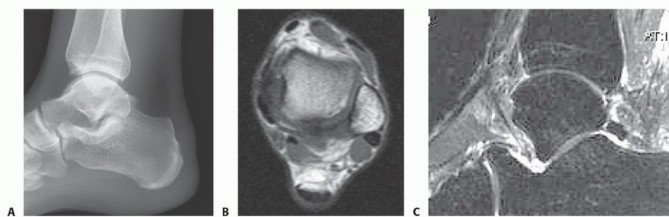

DEFINITION Large osteochondral defects of the talar dome, typically involving the talar shoulder (transition …

DEFINITION Osteochondral autograft “plug” transfer is a technique for treating full-thickness, localized arti…